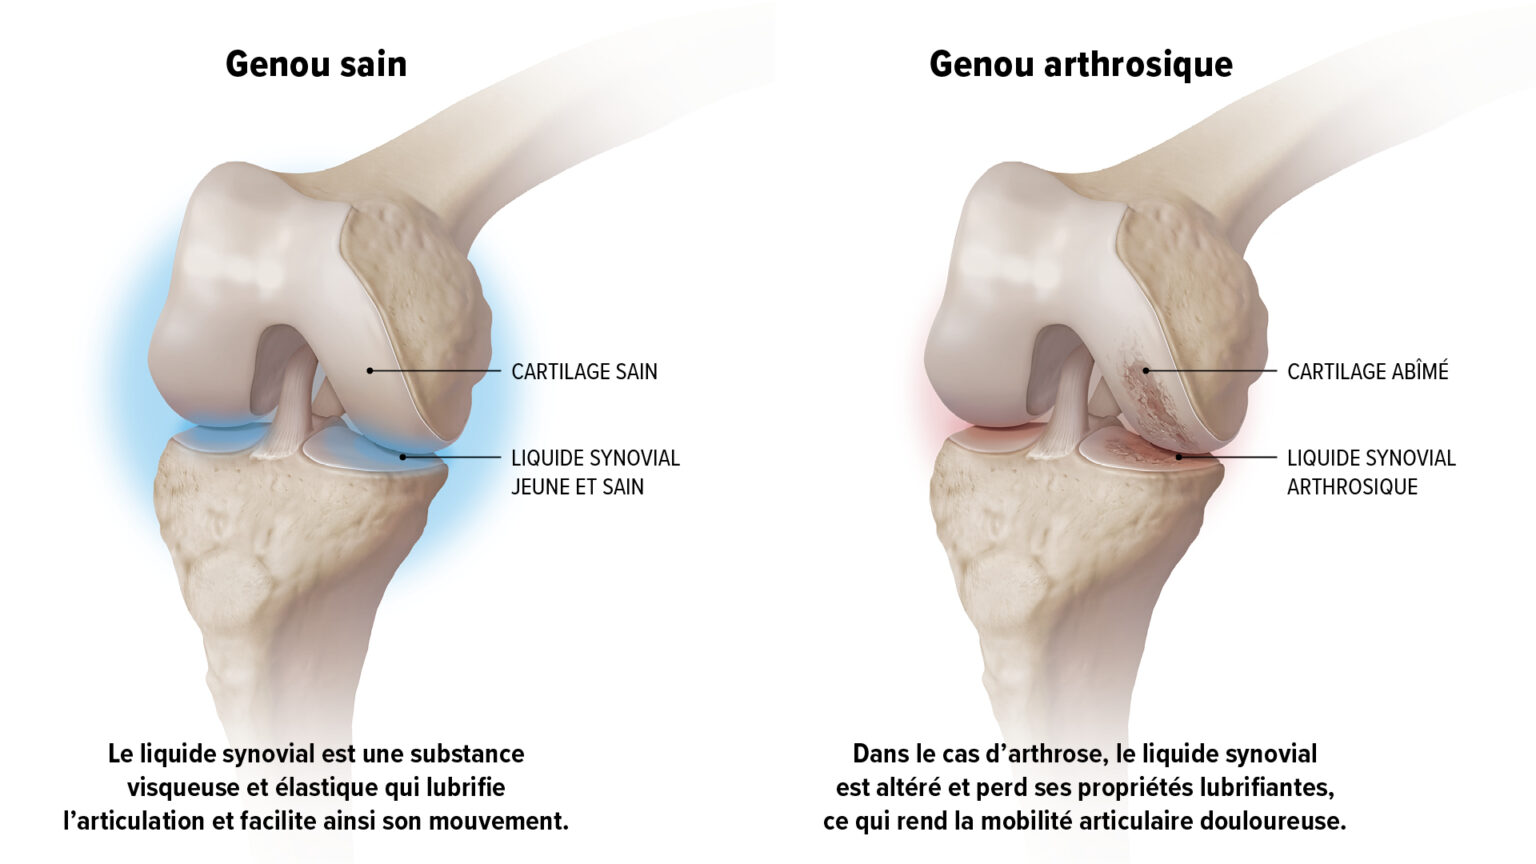

Le cartilage joue un rôle majeur car il protège l’articulation. Il recouvre les extrémités osseuses, facilite le glissement des os et absorbe les chocs. L’articulation baigne dans un liquide visqueux et élastique (viscoélastique) appelé liquide synovial, qui se trouve dans une cavité délimitée par la membrane synoviale. Ce liquide sert de lubrifiant et nourrit le cartilage.

L’arthrose du genou, ou gonarthrose, est principalement due à une détérioration du cartilage articulaire et à une altération des propriétés viscoélastiques du liquide synovial. En effet, l’acide hyaluronique, principal composant du liquide synovial, est dégradé. Le liquide synovial ne lubrifie plus le cartilage et n’absorbe plus aussi efficacement les chocs et les contraintes mécaniques infligées à l’articulation lors d’un effort. C’est alors que la douleur se fait sentir.